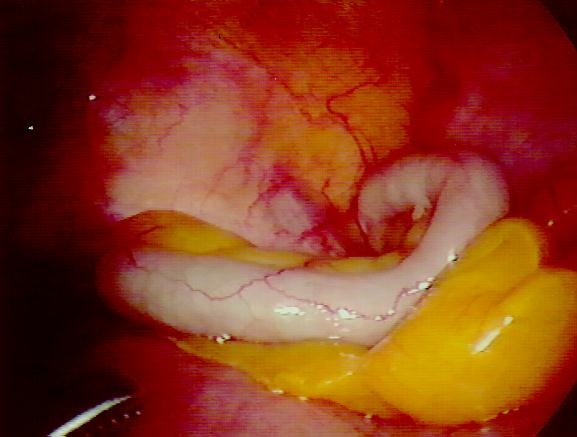

burst appendix symptoms

This image is titled burst appendix symptoms and is attached to our article about Chronic Appendicitis Symptoms, Causes And Treatments.

Be sure to visit the guide for more context and information about burst appendix symptoms, or read some of our other Health & Anatomy posts!

Chronic appendicitis is a medical condition caused by an inflamed appendix. The appendix is a small and very thin tube located at the junction of the small and large intestines. It is typically located in the lower right abdomen area. The appendix is normally four inches long and it doesn’t really have any specific purpose. Despite some opinions stating that the... Read full guide »